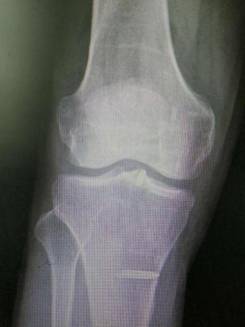

术前术后对比

全膝关节翻修术

全髋关节翻修术